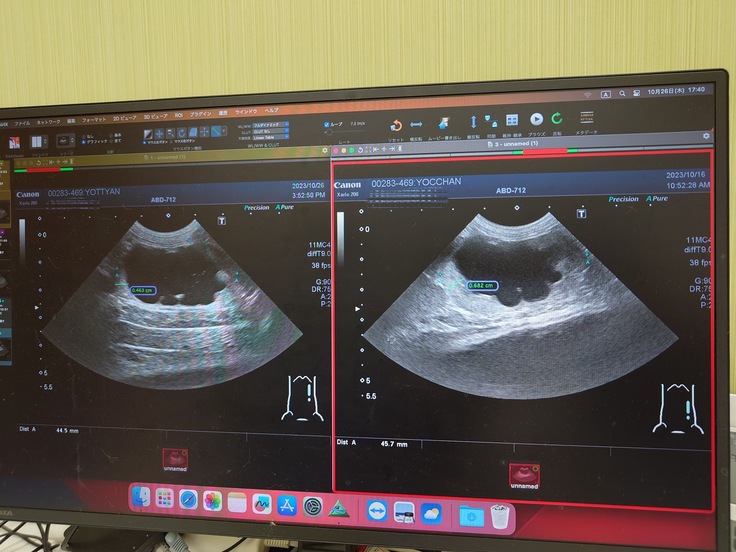

かかりつけの病院でエコー検査をしてもらったら寄生虫でも真菌でもない、別の2つ大きな病気が見つかりました。

◆1つ目は何かしらの原因で尿管が詰まっていて左側の腎臓と腎盂が肥大して左側の腎臓がほぼ機能していない状態。

◆2つ目は脾臓の肥大と膝裏のリンパの腫れが見つかり、細胞を取ってもらって顕微鏡で見てもらったら脾臓にリンパ腫がある可能性がある。

🐈エコー検査で腎臓と腎盂の肥大、脾臓も肥大していることが分かりました🐈